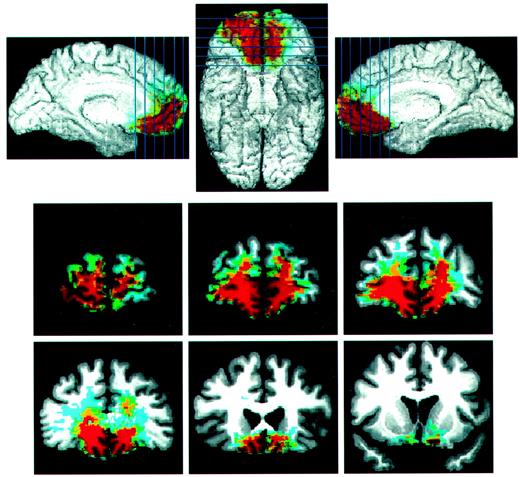

(Anatomy) Separate mapping of VM lesions for the group with Abnormal Gambling/Abnormal delay (A) (n = 5) and the group with Abnormal Gambling/Normal Delay (B) (n = 4). Red indicates an overlap of two subjects or more. The maximal overlap of lesions in (A) is seen spanning the whole extent of the mesial orbital surface of the frontal lobe. It reaches the posterior sector (coronal slice 4), where basal forebrain structures are found. However, in (B) the maximal overlap is mostly anterior extending only to slice 1 and 2. Slices 4 does not show any lesion. Coronal sections are arranged according to radiological convention, i.e. right is left, and vice versa.